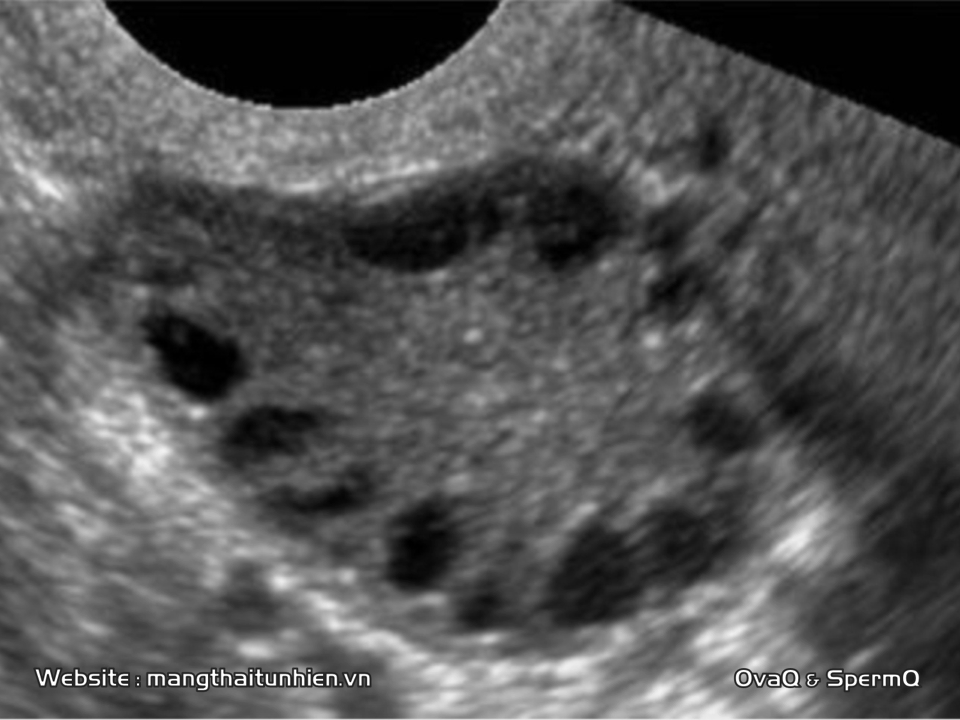

Серозоцервикс лечение

Серозоцервикс лечение 112 фотографий